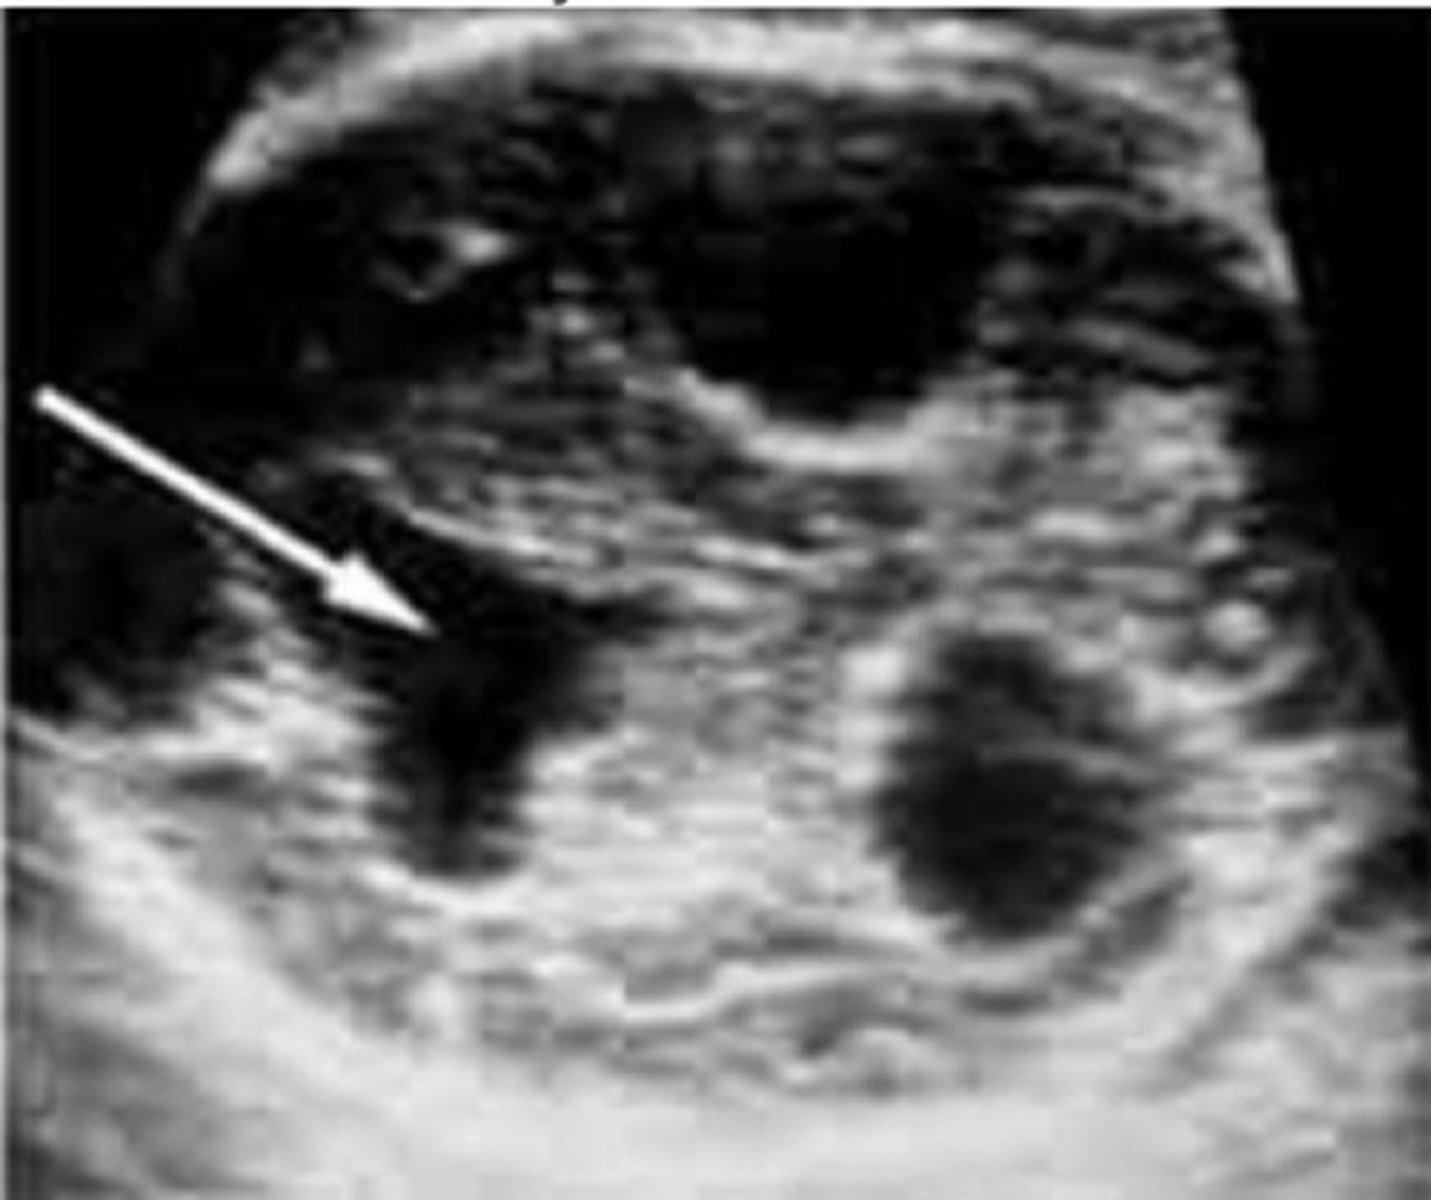

Hydrocephalus

Dilated ventricles

Dangling choroid plexus

Dandy-Walker Malformation

Defect in vermis of cerebellum that dilates the 4th ventricle

Splaying of cerebral hemispheres - enlarged cisterna magna